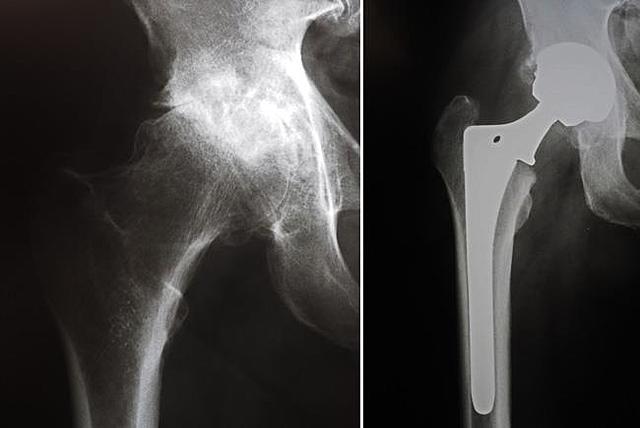

• Smith-Petersen

Smith-Petersen

introdujo el concepto de “artroplastia de molde” como una alternativa a la membrana de interposición.Comenzó utilizando una cúpula que se colocaba libre entre la cabeza femoral y el condilo, fue hecha primeramente de cristal que se rompía, posteriormente, en pyreglas, viscaloide y bakelita, un plástico primario que tampoco funcionó.

Wiles Phillips

implementa en una sustitución de cadera componentes emparentados de acetábulo y fémur a base de acero inoxidable en seis pacientes con la enfermedad de Still. El acetábulo se estabiliza mediante tornillo y el componente de la cabeza mediante un tallo, placa lateral y tornillos.

Se practicaba a través de una incisión anterolateral y consistía en una modificación tanto de la cabeza del fémur como del borde del acetábulo